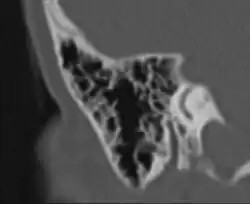

Die vom Mittelohr ausgehende Pneumatisation des Schläfenbeines ist mit dem fünften bis sechsten Lebensjahr weitgehend abgeschlossen. Ergebnis dieses Vorganges sind die pneumatischen Zellen, vor allem im Warzenfortsatz (Processus mastoideus). Es sind kleine, von Schleimhaut ausgekleidete Hohlräume, die durch unterschiedlich große Öffnungen miteinander und in der Gesamtheit mit dem Antrum mastoideum und damit mit dem Mittelohr in Verbindung stehen. Das Ausmaß der Pneumatisation des Schläfenbeines kann sehr unterschiedlich sein, es gibt Schläfenbeine mit fast komplett fehlender („gehemmter“) Pneumatisation, was meist als Folge häufiger Mittelohrentzündungen in der Kindheit anzusehen ist. Andererseits kann sich die Pneumatisation weit nach oben in die Schläfenbeinschuppe (Pars squamosa), nach vorne in den Jochbeinfortsatz (Processus zygomaticus) und in die Spitze der Felsenbeinpyramide ausdehnen. Es lassen sich im Warzenfortsatz typischerweise einzelne Zellgruppen oder Zellstraßen unterscheiden, die verschiedene Bezeichnungen tragen, wie Winkelzellen, Schwellenzellen, Terminalzellen usw. Dementsprechend werden bei ausgedehnter Pneumatisation Schuppenzellen (in der Schläfenbeinschuppe), Zygomaticuszellen (im Jochfortsatz), perilabyrinthäre Zellen (um das Labyrinth gelegen) und Pyramidenspitzenzellen unterschieden.